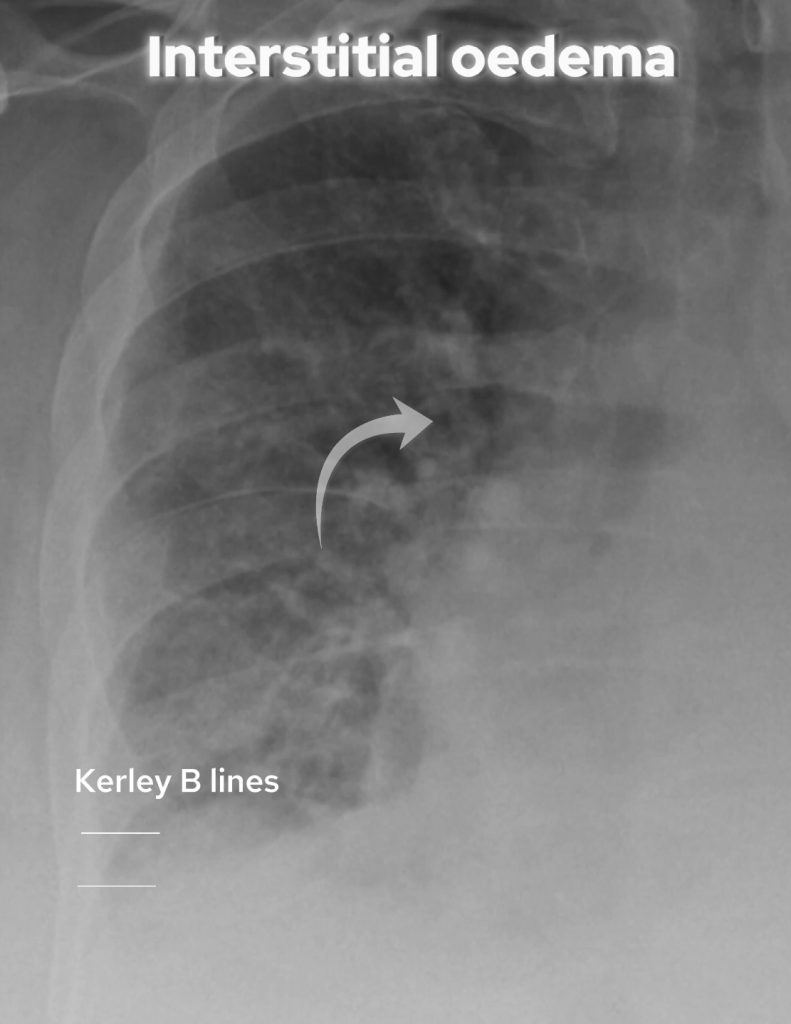

Interstitial Oedema:

• Thickening of bronchial walls, also known as peribronchial cuffing.

• Loss of airway definition creates a hazy appearance.

• Kerley B lines, horizontal lines at the lung bases, indicate interstitial thickening.

Look for thickening of bronchial walls and loss of definition of the airways. Kerley B lines were not present in this case but are seen as horizontal lines at the lung base reflecting interstitial thickening.